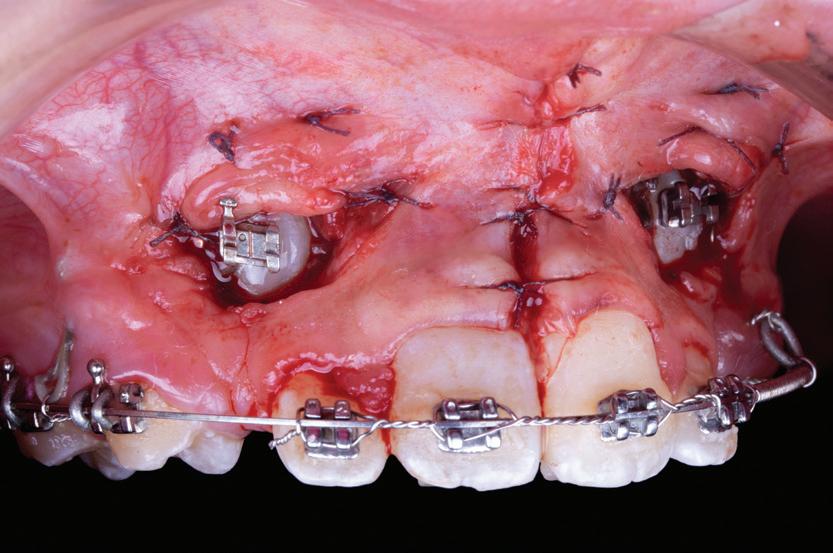

Lamboul repoziționat apical

Această tehnică este o opțiune atunci când nu există suficient țesut gingival keratinizat și este preferată atunci când caninul impactat este situat mezial față de incisivul lateral. Lamboul trebuie fixat și adaptat la dinte. Dezavantajele includ riscul de recesie și marginea gingivală neregulată, alături de necesitatea unei intervenții chirurgicale osoase extinse. Se efectuează incizii verticale, iar lamboul este deplasat într-o direcție laterală sau apicală. Se recomandă un design al lamboului în care baza și zona coronară sunt fie la aceeași lățime, fie mai înguste la bază, cu o grosime de 4-5 mm, astfel încât lamboul să fie suficient de lat meziodistal, extinzându-se cu 1,5 mm dincolo de unghiul dintelui (fig. 6, 7).

Osul acoperitor trebuie îndepărtat cu chiuretă sau freză diamantată pentru a expune porțiunea liberă a coroanei. Lamboul se poziționează apoi la CEJ și se fixează cu suturi periostale pentru o stabilitate mai mare. În funcție de gradul de impactare a caninului, se poate plasa un pansament parodontal, astfel încât țesutul să nu se închidă. Bracketul este plasat fie în momentul procedurii, fie la 10 zile postoperator. Dacă respectivul canin este situat prea apical, se preferă tehnica închi-

să. În general, deplasarea ortodontică începe la 4-6 săptămâni după expunerea chirurgicală. Când foliculul ce înconjoară caninul este larg, incizia lamboului trebuie făcută peste limitele acestuia, pentru a permite adaptarea optimă a lamboului la coroană și os. Pentru a determina buna adaptare a lamboului, atunci când buza se mobilizează, acesta ar trebui să rămână staționar.

6, 7. Utilizarea lamboului repoziționat apical pentru a gestiona caninii bilaterali cu impactare facială. După expunere, s-a practicat și frenectomia și au fost plasate bracketuri bilaterale (fig. 6). S-a realizat tracțiunea ortodontică, ce a permis poziționarea corespunzătoare a ambilor canini pe arcada superioară (fig. 7)